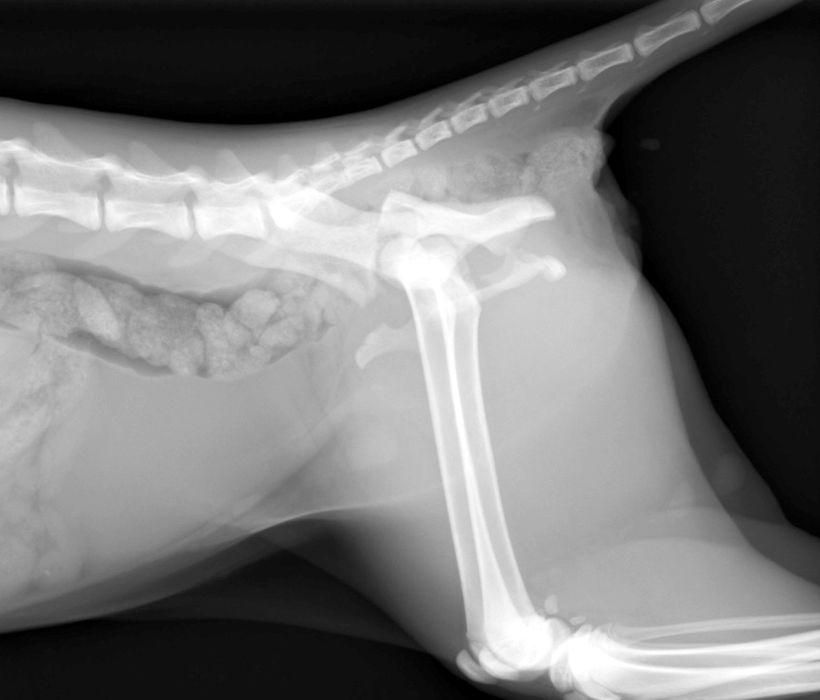

骨折治療について

動物も人間と同じように骨折や脱臼をします。

原因として交通事故などの大きな外力によるものもありますが、日本では小型犬が主体となっているため、ソファや抱っこしている所からの落下といった比較的小さな外力でも生じることが多くなっています。

骨折や脱臼の治療は、ギプスなどの処置のみで済むケースもありますが、ほとんどのケースは完全骨折や脱臼を生じますので、手術が必要となります。

当院における骨折治療は、動物のステータス、骨折の発生部位や分類などを考慮して「髄内ピン」「骨プレート」「創外固定器」を単独もしくは組み合わせて使用することで適当な固定力を得られるように施術しています。